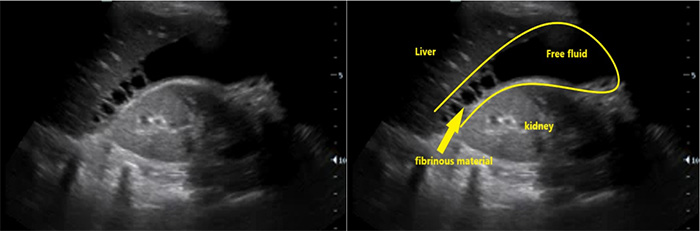

- Ascites (Fig. 6)

- Ascites is a common finding in many disease entities however in the patient with HIV from a TB endemic area, it is highly suggestive of TB.

- With or without fibrinous debris: OR 2.221

- Without fibrinous stranding: PPV= 73% NPV = 33%18

- With fibrinous stranding: PPV = 86% NPV= 41%18

Figure 8. RUQ free fluid with fibrinous stranding and hyperechoic liver lesions

- Hepatomegaly and hypo- or hyper-echoic lesions in the liver are commonly seen in HIV patients with EPTB but these findings are non-specific.23,24

- Free abdominal fluid will have irregular sharp edges as the fluid surrounds loops of bowel, while fluid contained in the bladder should have smooth rounded edges (Figure 7).